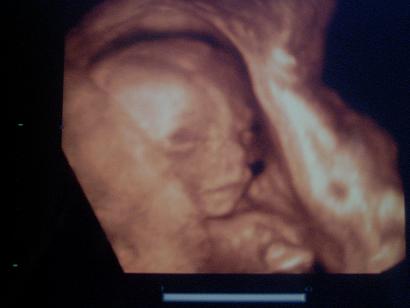

Én is felteszek képeket a kisfiúnkról. A képek a Hepinet rendelőjében készültek 21 hetesen:

Kép